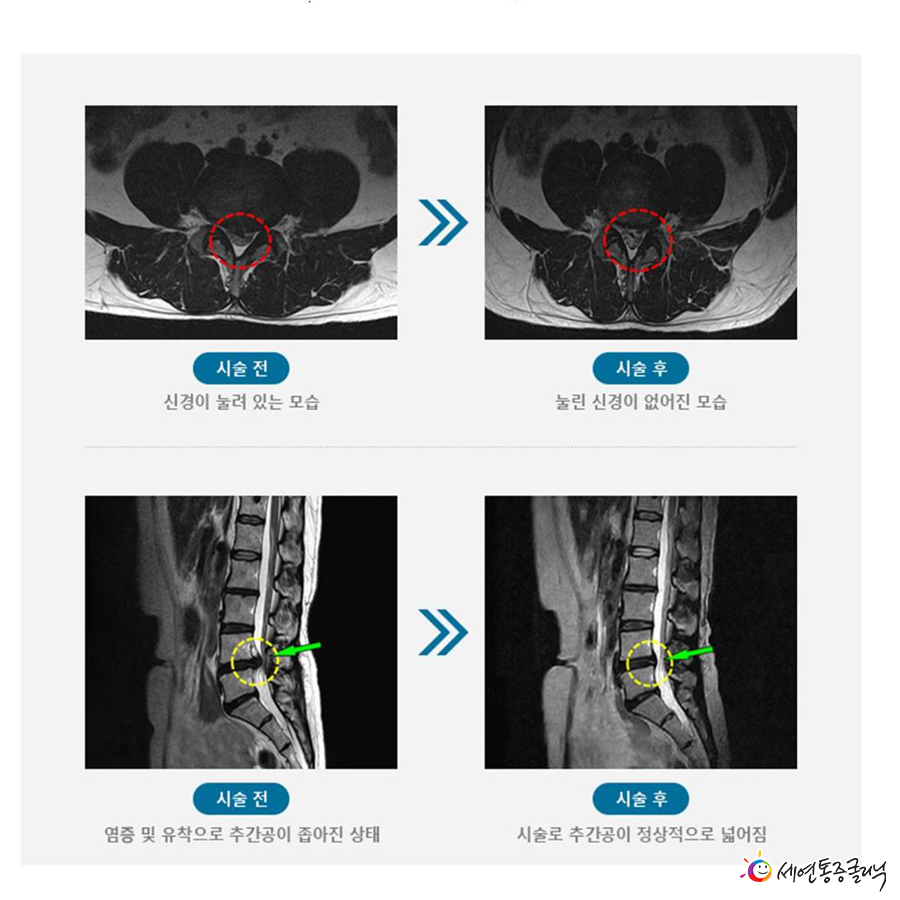

이번에는 추간공확장술에 대해 설명하면, 추간공(척추 사이 구멍)이 특정 원인으로 인해 좁아져 신경을 압박해 통증을 유발하는 척추관협착증의 비수술적 치료 방법입니다.

신경이 압박된 부분의 인대를 긁어내 공간을 넓혀 신경이 지나가는 통로를 확보해 좁아진 추간공의 염증을 제거하는 시술입니다.

추간공에 염증이 발생해 주변 신경 유착이 심해지고 인대가 두꺼워져 추간공을 좁아지게 만드는데, 신경을 압박하는 인대를 긁어내고 신경이 지나가는 통로를 확보해 통증 원인을 제거해주는 것이지요.